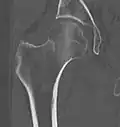

Subcapital fracture in a 92-year-old woman